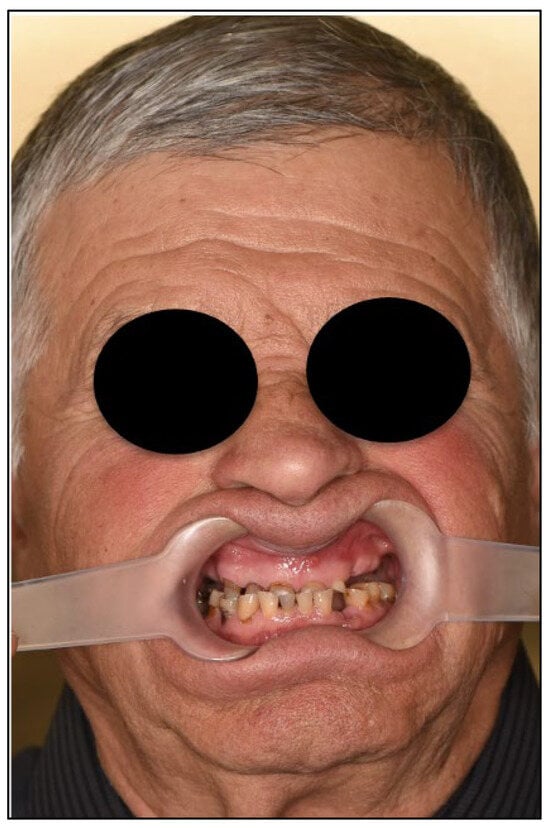

Figure 3.

Frontal close-up photography. Upper remaining teeth present with severe tooth loss, lateral teeth absence impairs bite and function.